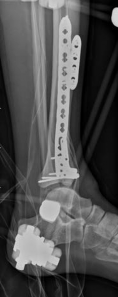

With the articular surface reconstituted, the surgeon's focus shifts to bridging the complex metaphyseal-diaphyseal dissociation. A pre-contoured anatomical locking plate is slid submuscularly or subcutaneously along the diaphysis using a MIPPO technique. The plate is positioned on the anterolateral or medial surface, depending on the preoperative plan and soft tissue constraints.

The distal portion of the plate is secured to the reconstructed articular block. It is imperative that the distal locking screws are placed parallel to the joint space, forming a rigid subchondral raft that supports the articular cartilage. Fluoroscopy is utilized extensively to ensure no screws have penetrated the joint. Once the distal block is secured to the plate, the diaphyseal segment is aligned. Length, alignment, and rotation are restored using manual traction or the femoral distractor. The proximal portion of the plate is then secured to the diaphysis using a combination of non-locking screws (to pull the bone to the plate) and locking screws (to create a fixed-angle construct). The working length of the plate is maximized by leaving several screw holes empty over the zone of comminution, promoting secondary bone healing.

Digital templating is utilized to select the appropriate implant. For a fracture extending into the diaphysis, an extra-long anatomical distal tibia locking plate is required. The surgeon must determine whether an anterolateral or medial plate (or dual plating) will provide the optimal biomechanical construct based on the fracture morphology. The trajectory of the distal locking screws must be planned to provide a subchondral raft supporting the articular surface without penetrating the joint space. Furthermore, the availability of bone graft or orthobiologics must be confirmed, as elevating impacted articular segments will leave a metaphyseal void requiring structural support.